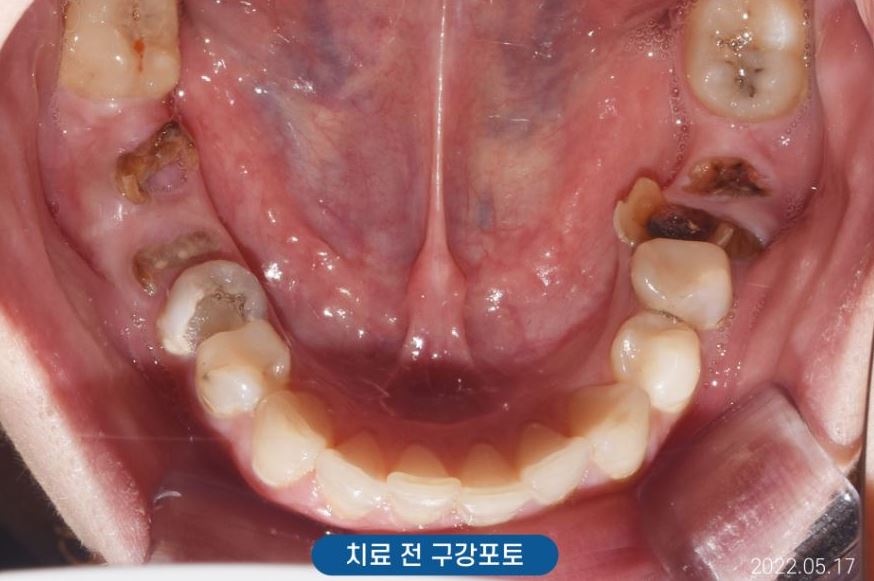

조금 더 정확한 검사를 하기 위해

X-ray(Panorama)와

구강포토를 촬영하였습니다.

아래쪽 양쪽 어금니와

위쪽 사진 기준 왼쪽 어금니가

많이 손상되어

치아머리가 더의 보이지 않았는데요.

식사의 어려움은 없으셨을까요?

않타깝게도 부러진 치아의 치질이

거의 없는 상태였기에

치아를 살릴 수 없어

양쪽 위 아래 어금니 임플란트로

계획을 세우게 되었습니다.